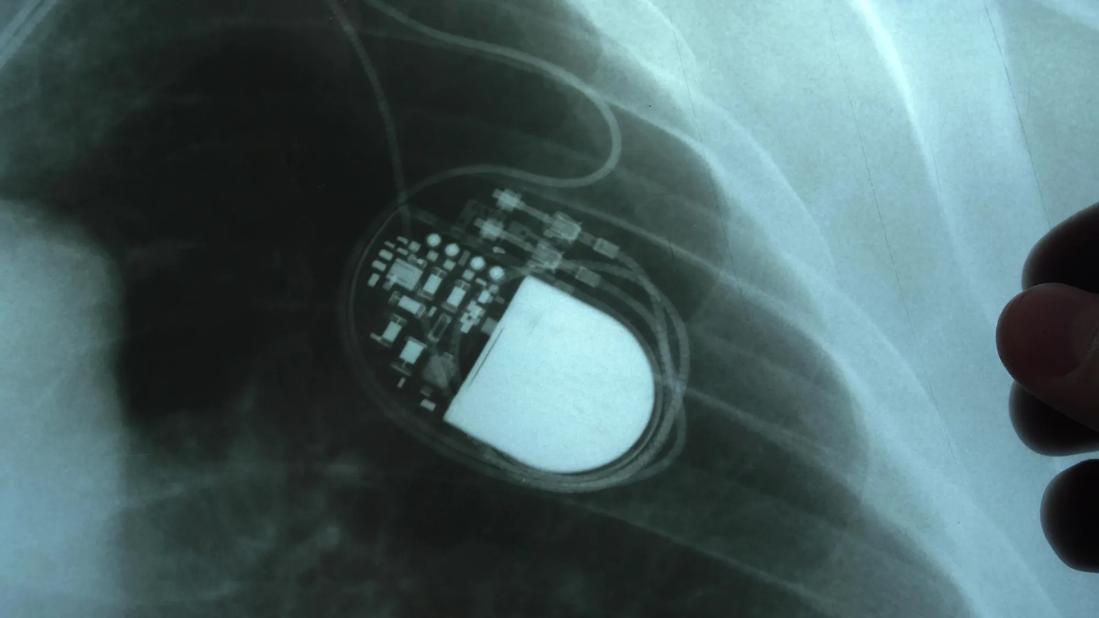

Pacemakers are usually inserted beneath the skin of your upper chest near your shoulder. In most cases, wires — also known as leads — run from the device into your heart. You may need one, two or three leads depending on your condition. People are usually discharged from the hospital the same day after receiving one.

Pacemakers operate automatically. Little antennas in the pacemaker allow doctors to collect data about your heart’s rhythm and the pacemaker’s function during follow-up. They can then customize your pacemaker’s activity to fit your needs as necessary.

- They’re surprisingly small. “Today’s pacemakers are about the size of a big tablespoon,” Dr. Varma says. That’s small enough that you’ll rarely feel it.